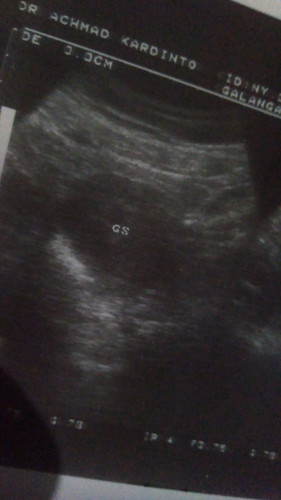

Mkanan apa ya yg bikin janin selalu tumbuh kuat untuk trimesti pertma ku aku ingin yg trbaik bun

Ini adalah anak pertma saya dr 1 tahun pernikahan